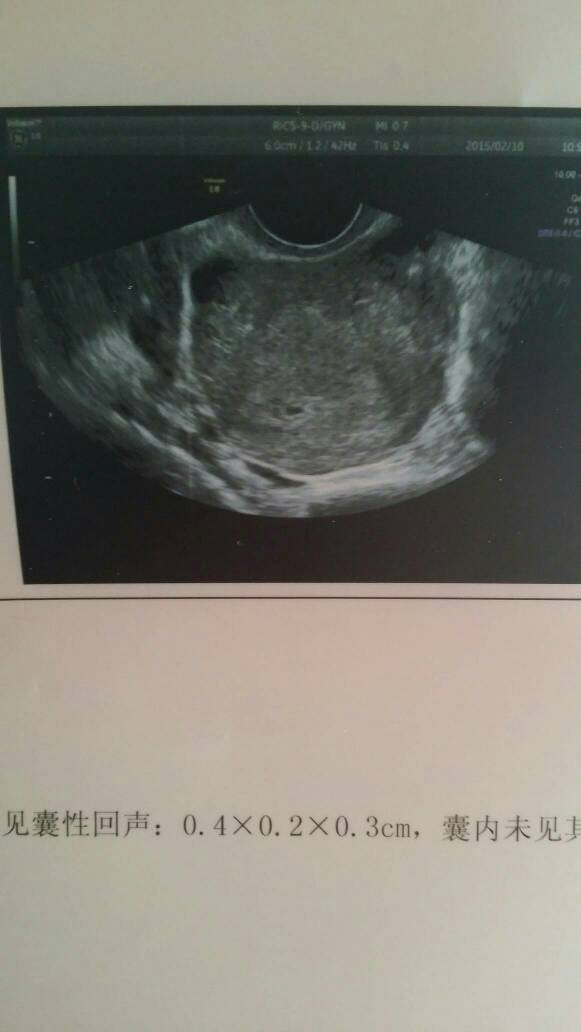

有懂的吗,帮我看看,我的孕囊是男孩还是女孩,谢谢! 有懂的吗,帮我看看,我的孕囊是男孩还是女孩,谢谢! 点击展开 宝遥儿 2015-02-11 13:15 为您推荐: 其他回答 不准的、、、 安 分守己ヽ 2015-02-11 22:08 还早着呢… 宝宝希望你健康! 2015-02-11 15:28 都看不到孕囊😓😓 奇葩女神蹦擦擦。 2015-02-11 14:49 谁说看孕囊能看出男女??? 幸运女神. 2015-02-11 14:43 不科学的! 小甜猫 2015-02-11 14:24 加载更多 相关问题 怀孕7周十4,孕囊3 7x2 4x1 1,谁能帮我看看是男孩还是女孩 宝妈们帮我看看,我的宝贝是男孩还是女孩 7周孕囊是42*22*19 9周是42*55*32 10周 请懂的医生或者妈妈帮我看看:这是四维彩超还是三维的?男孩还是女孩?